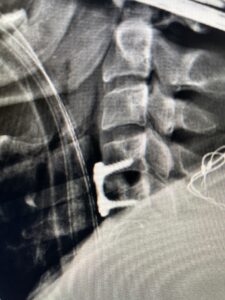

Fig. 3 Intraoperative lateral cervical X-Ray demonstrating C4-5 ACDF

This 47-year-old male who four months prior was lifting weights developed sharp pain in his neck. After that he developed progressive numbness in his arms, neck pain and headache. He said that the right arm was worse than the left. On examination the patient had long tract weakness on the right side which included his triceps, finger extensors, hip flexors, and dorsiflexors. The patient did not have hyperreflexia. MRI (Fig. 2) demonstrated a massive, extruded disc herniation with severe cord compression. The patient because of progressive myelopathy and spinal cord compression was indicated for anterior cervical discectomy and fusion at C4-5 (Fig. 3). Patient had significant improvement of weakness and numbness post operatively.